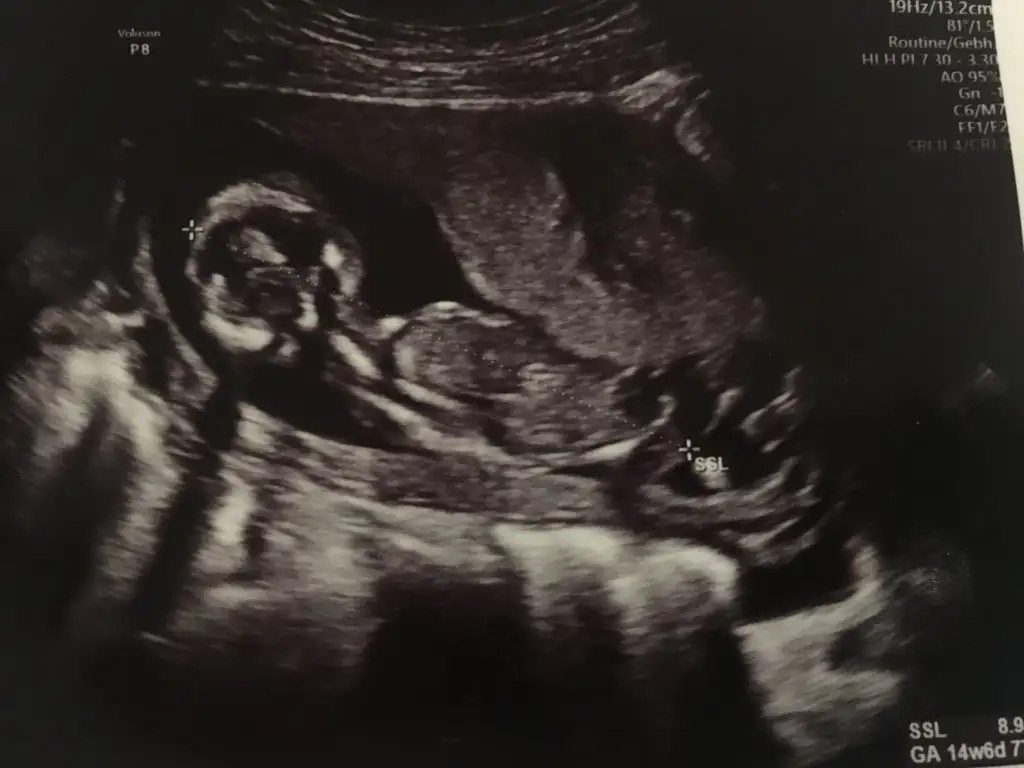

Nub için 12 13 hafta olmalı bacak arası boş görünüyor sanki kıx gibi varsa istediğim haftlarıda paylaşınMerhaba hanımlar bu topiği yeni keşfettim. Düşünenden yardımcı olandan Allah razı olsun inşallah. Ben yurtdışında yaşıyorum ve yaşadığım ülkede 20. Haftadan önce cinsiyet bakmıyorlar. Benim daha bir ayım var ve çok merak ediyorum. Öncelikle rabbim hepimize hayırlı ve sağlıklı evlatlar nasip etsin inşallahBenim en son doktor randevum 2 hafta önceydi 14+ 2 de son aldığım ultrason fotoğrafını ekliyorum. Yorumlayabilir misiniz rica etsem Eki Görüntüle 2652301

Kız olabilirMerhaba bu da bizim 14. Hafta görüntümüz bakabilir misiniz?

Erkek sanki 11 12 13 hafta olmalı 14 değil emin değilimMerhaba bu da bizim 14. Hafta görüntümüz bakabilir misiniz?